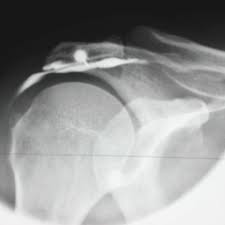

Une infiltration articulaire consiste à injecter dans l'articulation douloureuse un produit (acide hyaluronique ou produit à base de cortisone) dont l'objectif est de réduire vos phénomènes douloureux.

2) l'introduction de l'aiguille

3) la vérification du bon placement de l'aiguille par une ponction de liquide et/ou une injection de produit iodé (en dehors de tout problème allergique)

4) l'injection du produit.